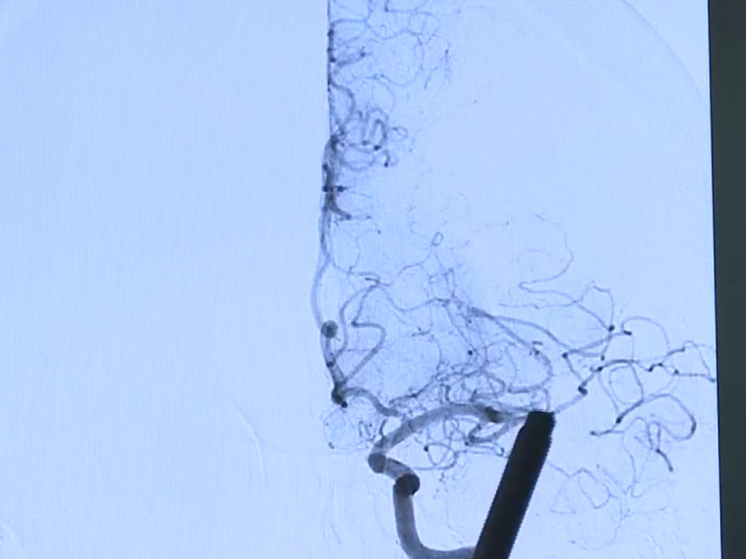

Фото: ГТРК Смоленск

Смоленская область принимает участие в Неделе сохранения здоровья головного мозга.

Врачи отмечают важность профилактики различных заболеваний мозга, включая нервно-мышечные заболевания, эпилепсию, рассеянный склероз, болезнь Паркинсона, деменции, хроническую ишемию головного мозга и инсульт.